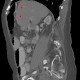

Da die unterschiedlichen Abstufungen und deren Veränderung allerdings mit bloßem Auge häufig nicht genau zu erkennen sind, haben sich die Wissenschaftler eines Tricks bedient: Sie setzten eine CT-Perfusionsmessung ein, durch die wenig durchblutetes Infarktareal gut zu erkennen ist. Anschließend nahmen sie eine Dichtemessung in ebendiesem Bereich – in einem sogenannten CT-Fenster – vor, sodass hier kleinere Grau-Abstufungen zu erkennen waren und sich die Wassermenge genauer bestimmen lies.

Der Haken an der Sache: Die Graustufen des Gehirns unterscheiden sich von Mensch zu Mensch – nicht jede Schattierung ist also auf neu eingelagertes Wasser zurückzuführen. Aber auch dafür fand das Forscherteam eine Losung: Da die rechte und die linke Hirnhälfte auf einem CT-Bild in der Regel gleiche Schattierungen aufweisen, verglichen die Wissenschaftler die Grauwerte im Bereich des Schlaganfalls mit denen im spiegelbildlichen Bereich der gesunden Hirnhälfte. So konnten sie für jeden Patienten individuell bestimmen, ob der Insult mehr oder weniger als viereinhalb Stunden zurücklag.